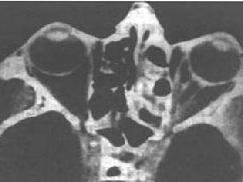

眼眶真菌病发病率极低,常见的致病菌有毛霉菌、曲霉菌和隐球菌,还有放线菌、青霉菌等。当真菌寄生在人体正常组织内时,如鼻窦、结膜囊。一般不致病,当机体免疫力下降、外伤、大剂量皮质激素或广谱抗生素的广泛使用,寄生的真菌可致病。